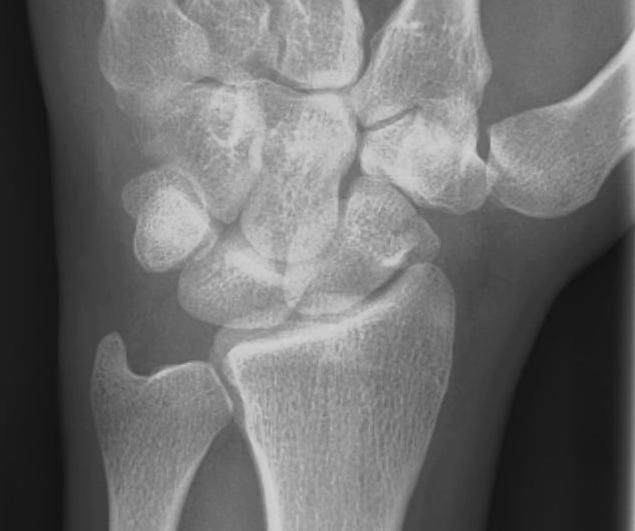

X-ray

5 images

- PA / lateral

- PA in 45° oblique pronation / PA 45o oblique supination

- PA in ulna deviation

Scaphoid waist fracture 1 mm displaced

Scaphoid fracture with significant displacement

Scaphoid proximal pole fracture